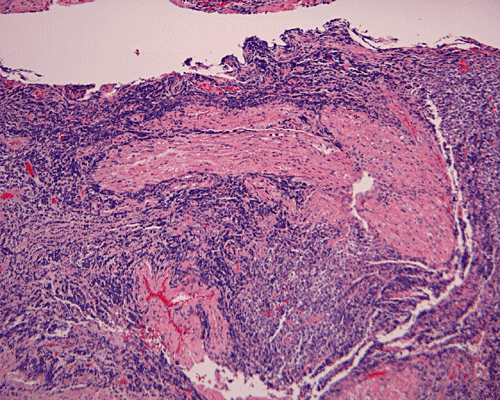

The surgery removed several irregular fragments of tan, soft tissue for examination that were 2.5 x 1.2 x 1.0 cm in toto. Histologically, the lesion is a highly cellular neoplasm with tumor cells packed in solid sheets and without a specific architectural pattern (Panel D). Small, focal necrosis is also present (not shown). The tumor has rich vascularity and the endothelial cells seem to be active (Panel E). Almost all the tumor cells have only a thin rim of amphophilic cytoplasm, large nuclei with prominent nucleoli (Panel E and F). Clear cytoplasm is present in some tumor cells. In general, the cells do not look epithelioid or spindle. In some of the tissue fragment, the tumor shows invasion into the peripheral nerve root with dissection of the nerve fibers (Ú in Panel G and H). This phenomenon is well demonstrated by reticulin stain (Panel I) and immunohistochemistry for neurofilament proteins (Panel J). About half of the tumor cells are strongly positive for vimentin (Panel K). There is also scant positive tumor cells for S100 protein (Panel L) and cytokeratin AE1/3 (Panel M). The tumor cells are negative for neuorfilament proteins (Panel K) and smooth muscle protein (Panel N).

The tumor under discussion is undifferentiated or poorly differentiated. The scant positive cells for S100 protein cannot strongly support a schwann cell origin. The lack of expression of EMA does not support a peirneurial or meningothelial origin. Therefore, these results do not suppoart a diagnosis of malignant peripheral nerve sheath tumor (MPNST) or meningioma. Both entities are unusual in this age group. While many MPNST may express cytokeratin AE1/AE3, the expression of a scant amount of cytokeratin does not totally rule out the possibility of a MPNST. Although the peripheral nerve bundles are diffusely infiltrated by the tumor as shown in Panel G and H and may suggest a malignant tumor arising from a nerve trunk, there is a lack of solid evidence to prove that this tumor is arising from a nerve trunk. Although a MPNST is suspected, the age and location is quite usual for this entity. The tumor under discussion is best classified as an undifferentiated sarcoma.